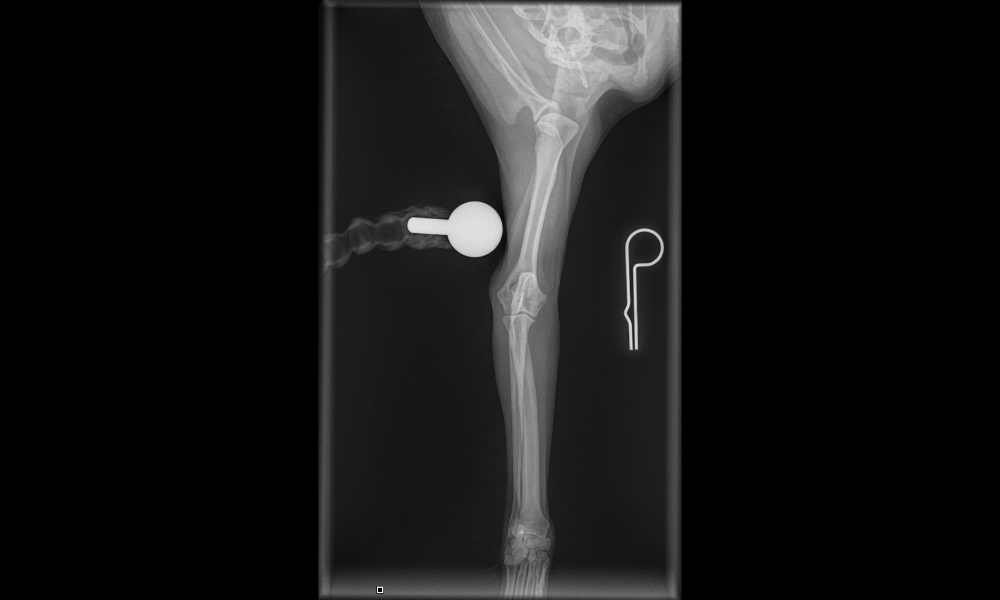

“The attending veterinarian conducted an X-ray examination and confirmed that the puppy had suffered a fracture to its right front leg.

“The doctor further stated that the injury was recent and had occurred within the past one week, and subsequently issued a written medical report to support these findings,” Kavitha said.